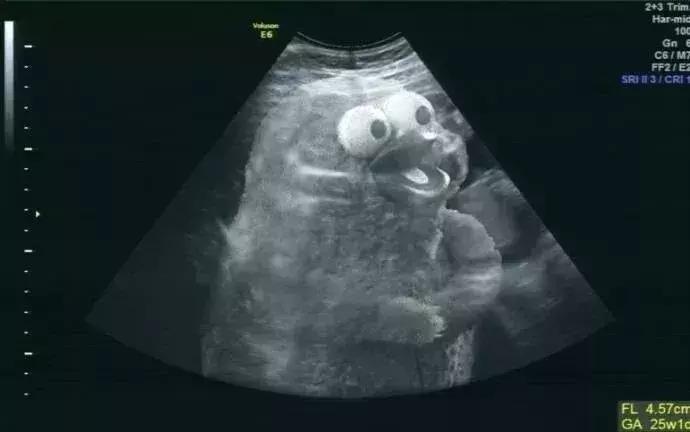

胎儿超声检查更是超声检查的独有优势,20年前大家还不太能接受超声胎儿检查,担心对孩子有影响,不过现在大家都有了超声孕检的观念,在孕期中孕大排畸检查(三级筛查)已经广为大家所接受,对国家优生优孕有重大的促进作用。不过早中孕系统筛查也非常重要,而目前仍未被大家所重视。

提示:早中孕期胎儿超声筛查是十分有必要的。

许多严重的胎儿畸形,如单心室、心室发育不良、心内膜垫缺损等,都可以在早中孕周被筛查出来,所以早中孕的检查非常重要。但仍需要有一定的技巧和技术依赖性,目前仍掌握在少数高水平超声医生手上。